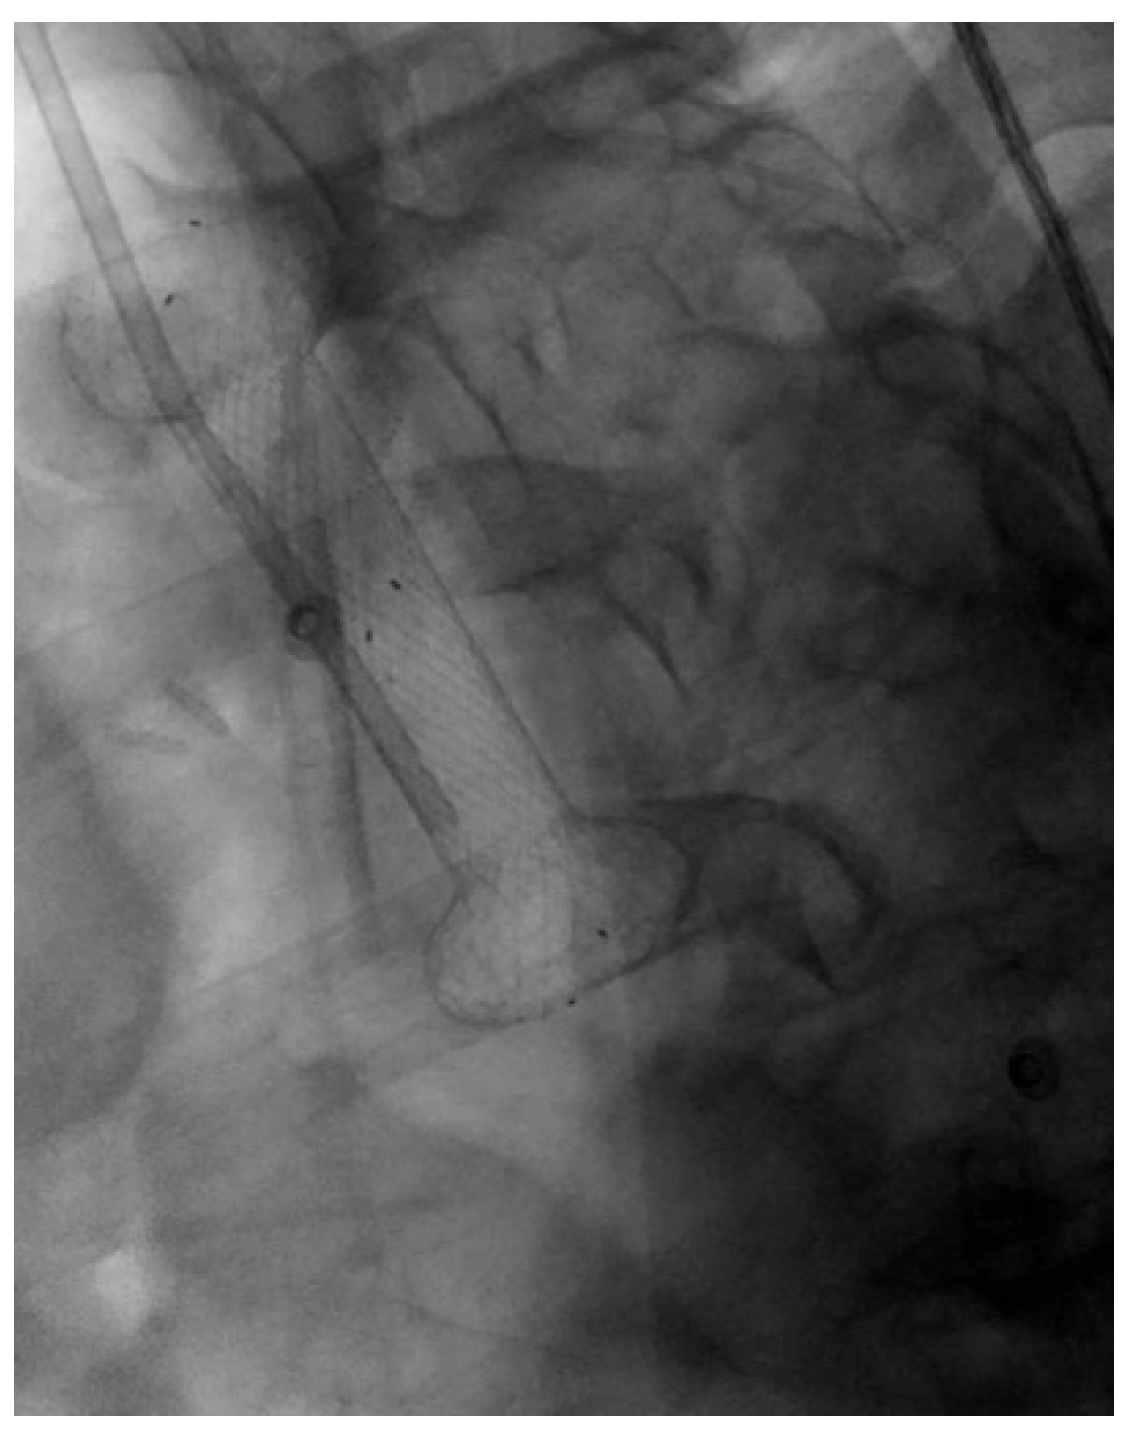

4.1.2. LAMS

Indication and Mechanism of Action

- Direct technique: puncture of the jejunal loop with a 19G needle and contrast injection to confirm position [126].

- Device-assisted EUS-GE: balloon or enteroscope passed across the stenosis to aid EUS visualization and targeting [127].

- Wireless Endoscopic Simplified Technique (WEST): described by Bronswijk et al. in 2020 and currently the most widely used technique [128], this approach involves jejunal distension via a nasoenteric tube with saline and dye, followed by “free-hand” single-step LAMS deployment under EUS guidance [128].